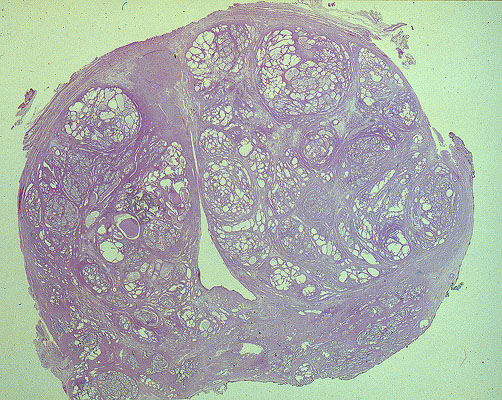

Benign prostatic hyperplasia, histology

The prostate contains groups of glans composed of cells that appear hyperplastic and protrude into the lumen.